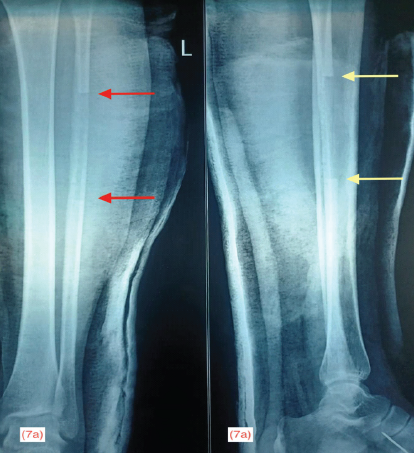

shows the immediate post-operative radiograph of the foot protected with below knee cast. Fig. 7 shows the radiograph of the graft donor site in anteroposterior and lateral projection.

Figure 7: Immediate post-operative radiograph of the hemifibula bone graft donor site in anteroposterior projection with red arrows marking the length of graft (a) and lateral projection with yellow arrows marking the length of graft (b)